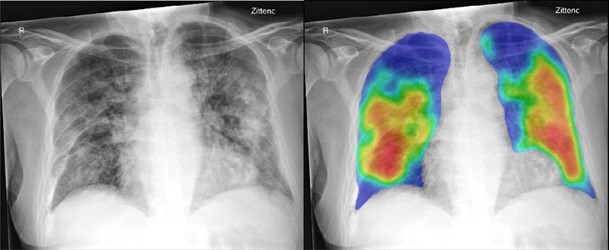

From the Radiology study, "COVID-19 on the Chest Radiograph: A Multi-Reader Evaluation of an AI System."

Left: 74-year-old male with positive RT-PCR test for SARS-COV2 viral infection. (A) Frontal chest x-ray (B) The artificial intelligence (AI) system heatmap overlaid on the image showing the pneumonia related features. The AI system score for this subject is 99.8. Right: 30 year old male with negative RT-PCR test for SARS-COV2 viral infection. (C) Frontal chest x-ray (D) The artificial intelligence (AI) system heatmap overlaid